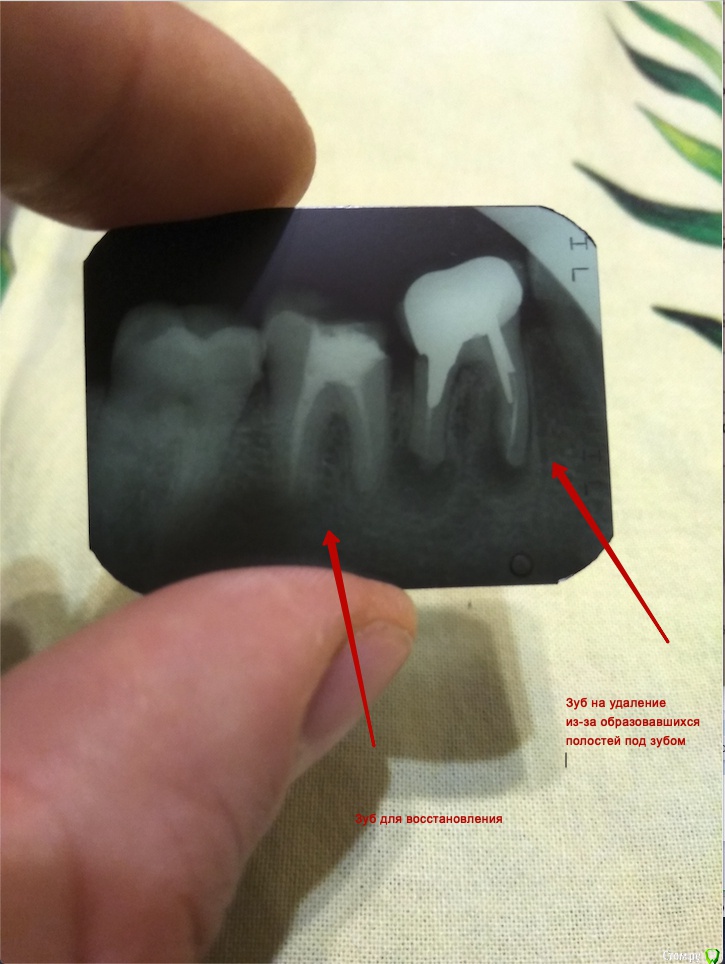

Пришел к врачу для восстановления стенки коренного зуба, а он после снимка заявил что другой, соседний зуб идет на удаление.

Зуб который должен по словам доктора идти на удаление, содержит коронку. Ее установили в 2013 году т.е. 6 лет назад и он никак пока не болит.

Прикрепляю снимок зуба.

post-56697-0-59934600-1545505500_thumb.jpg

Зуб под коронкой надо удалять и не ждать пока начнет болеть. Считайте он уже давно болит, но вы этого не чувствуете.

В соседнем зубе провести ревизию каналов и восстановить ортопедически.